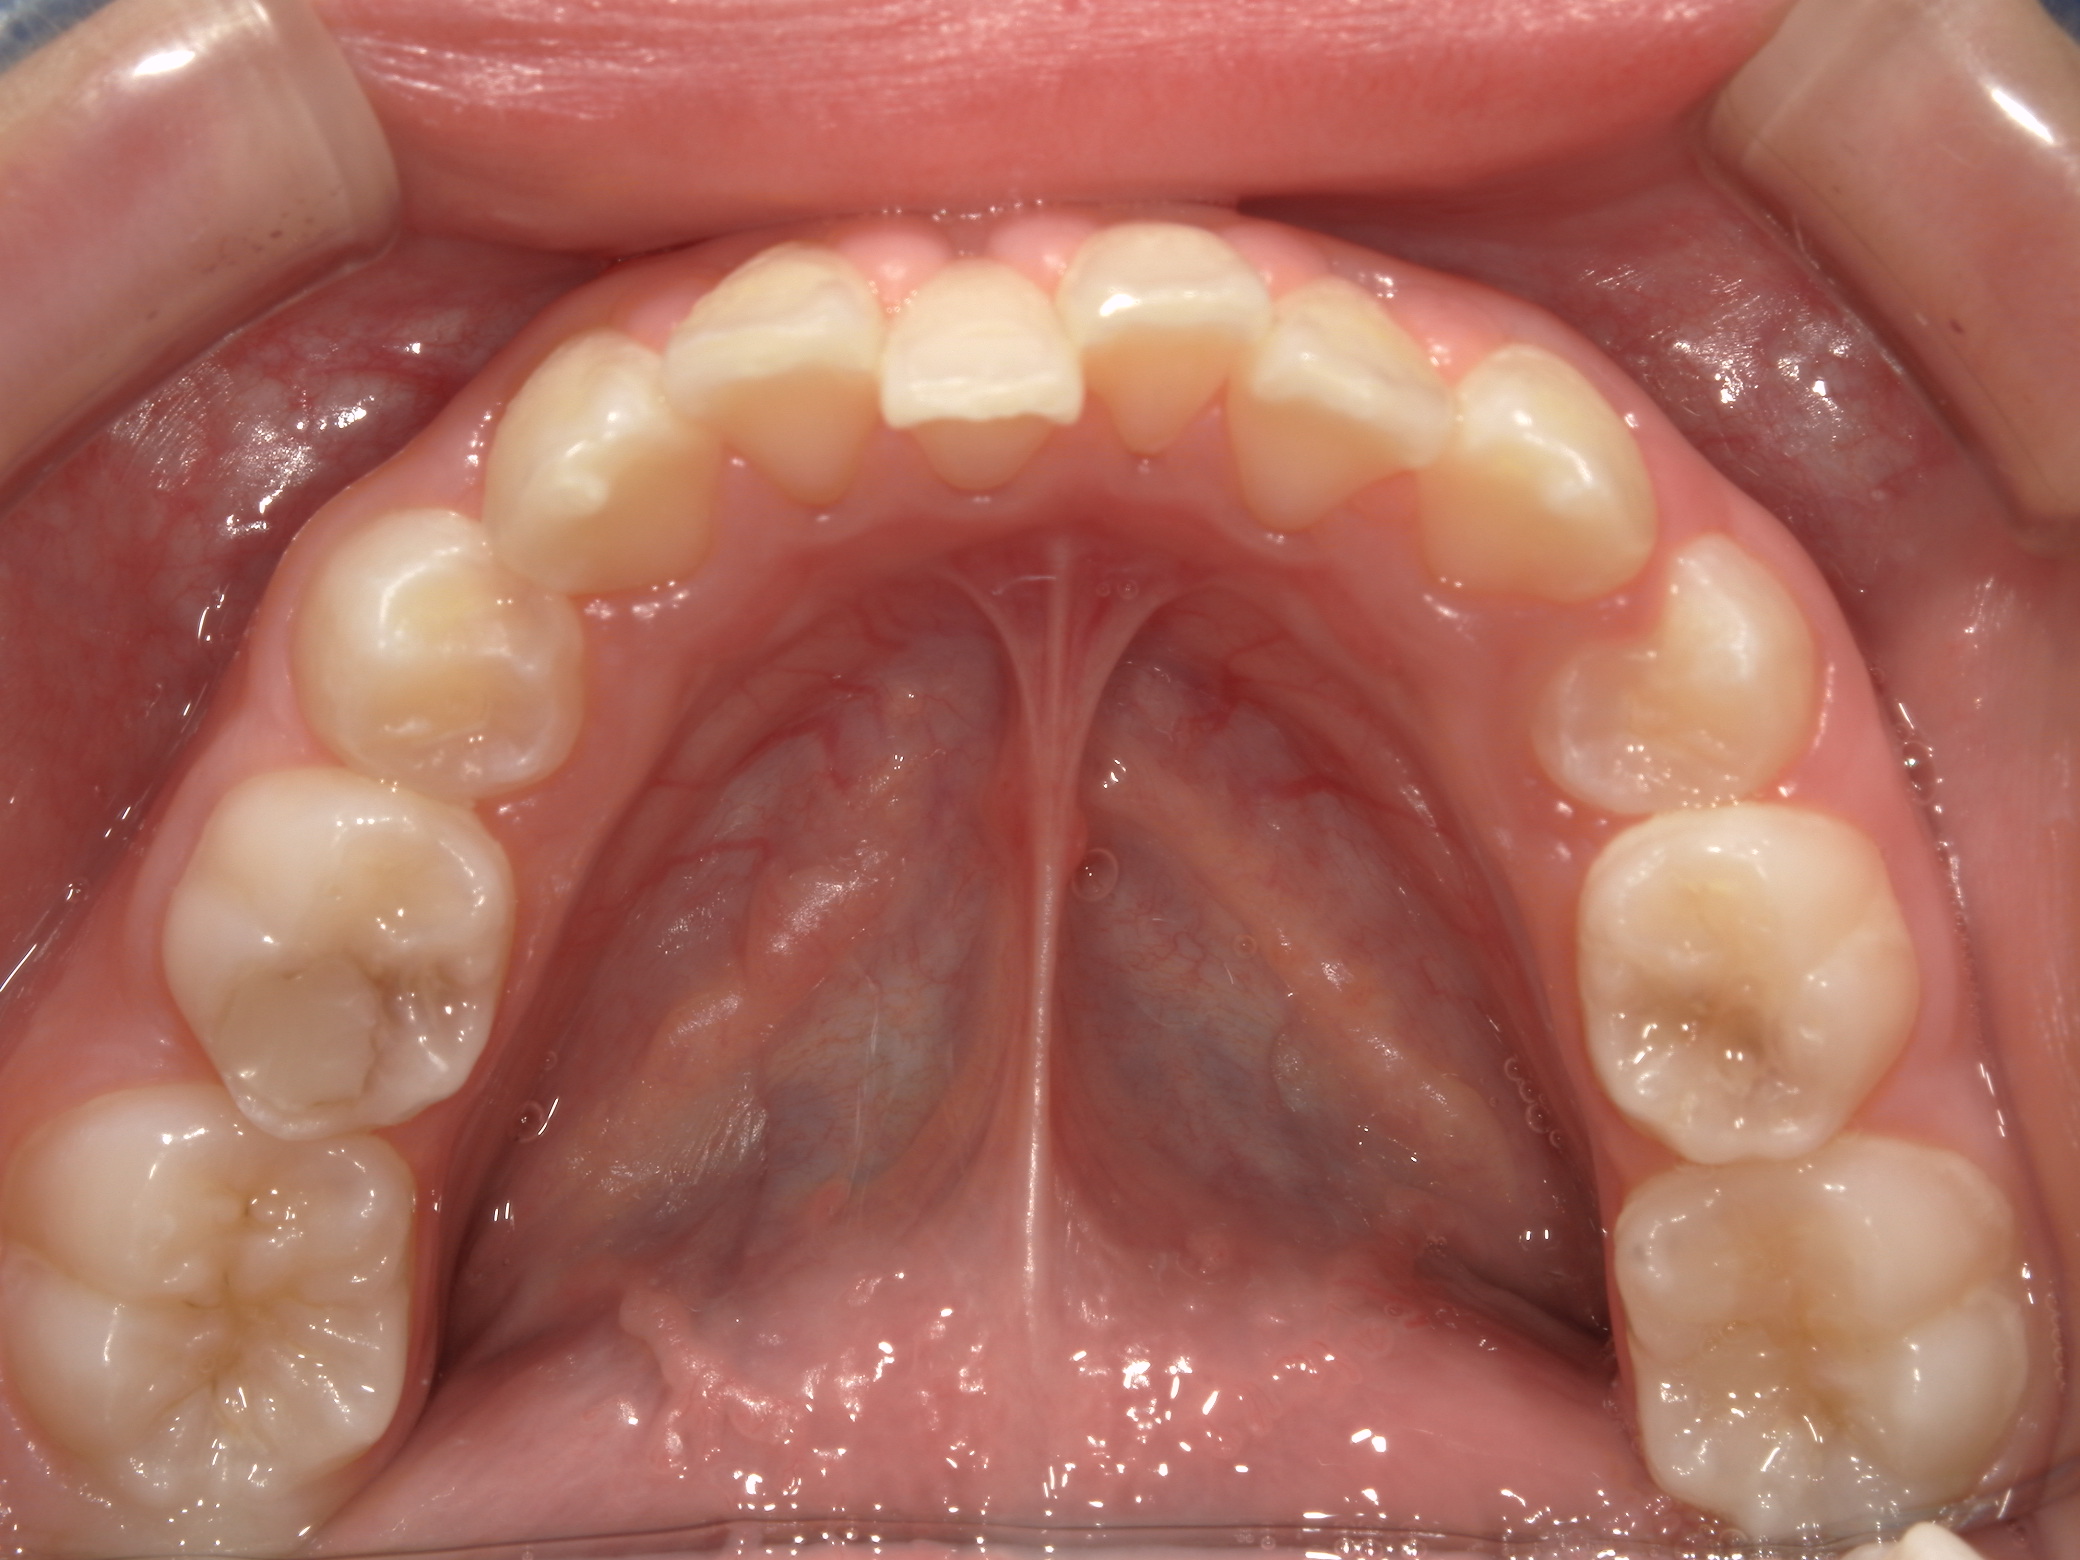

上歯前突+叢生症例 成長期

主訴 | 口元の突出感と歯並びが気になり、将来的な咬合状態を整える目的で来院された患者様です。 |

---|---|

診断結果 | 11歳1か月の女性。骨格的には日本人標準に近く、歯性の上顎前突および叢生が認められました。上下顎ともに歯列のスペース不足があり、永久歯の萌出や歯列の整列に支障をきたす可能性があると診断されました。 |

治療内容 |

|

治療後の経過 | 動的治療終了後は、上下顎の歯列が整い、口元の突出感と叢生が改善されました。審美的・機能的なバランスが取れた状態となり、現在は取り外し式リテーナーを使用し、保定期間に移行しています。 |

治療期間 | 動的治療期間:2年6か月 通院回数:25回 |

治療費用 | 720,000円 |